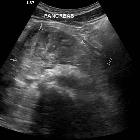

CT

- direct signs

- hypodense laceration or comminution of the pancreatic parenchyma

- heterogeneous parenchymal enhancement

- enlargement of the pancreas

- fluid collections (pseudocyst, abscess or hematoma) communicating with the pancreatic duct

- secondary signs

- peripancreatic fat stranding, fluid or hematoma between the pancreas and splenic vein

- peripancreatic fluid

- thickening of Gerota’s fascia

- injury to the pancreatic duct may not be seen directly but is inferred by the grading of the injury